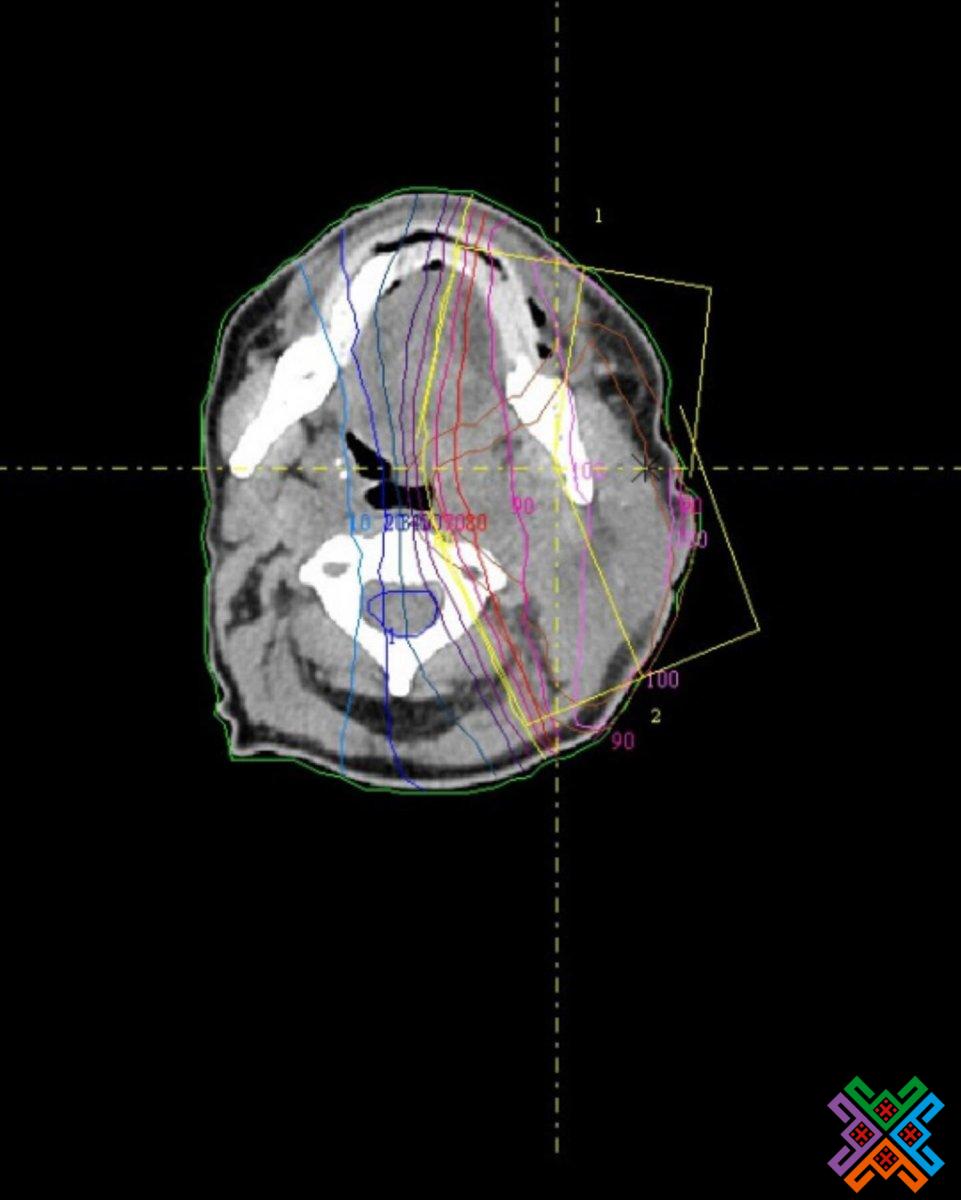

- Лікарі точно визначають розташування пухлини.

- Проводять топометричну підготовку, аби розрахувати потрібну дозу й час опромінення.

- Застосовують КТ-топометрію, щоб перенести розрахунки з плану на тіло пацієнта якнайточніше.

- мінімальний вплив на здорові тканини;

- максимальна ефективність;